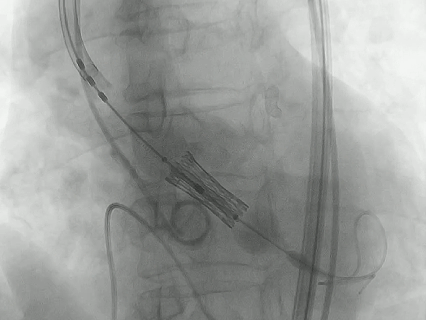

手术当天,夏淑东主任先从右侧股动脉穿刺置入血管鞘,在血管里搭建了一条 「临时通道」。接着用 20 mm 的球囊对狭窄的瓣膜进行预扩张,仿佛用打气筒把生锈的阀门稍微撑开一点。

最关键的一步是输送瓣膜过弓。王奶奶的主动脉弓严重弯曲,团队凭借精湛的技术,让装载着瓣膜的输送系统顺利 「过弯」 并跨瓣。瓣膜定位后,医生精准释放了 23 mm 的人工瓣膜,在正确的位置安装好了新的 「心门」。